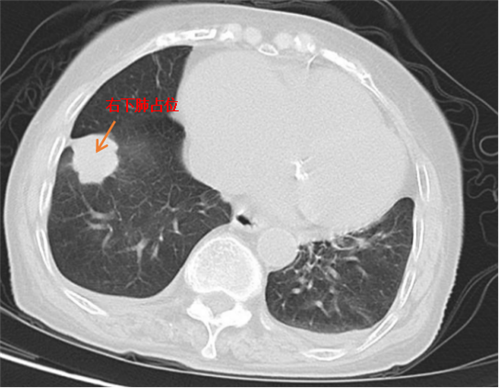

近日,83 岁的市民尹某因心慌、胸闷入住我院急诊科。入院后胸部 CT 显示右肺下叶占位,建议增强扫描,部分胸椎椎体高度减低。呼吸与危重症医学二科会诊后考虑肺恶性肿瘤不能排除,遂转入该科室进一步诊治。